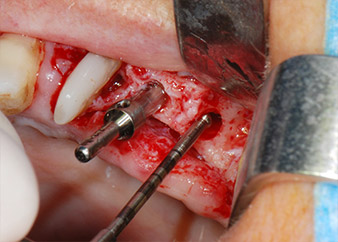

En el siguiente paso, los lechos del implante se prepararon en las posiciones 25 y 26 con instrumentos rotatorios, utilizando un contra-ángulo con un coeficiente de transmisión de 20:1 (WS-75 L, W&H), junto con el nuevo potente motor de implantes Implantmed de W&H (figuras 8 y 19).

La preparación final junto al seno se realizó de nuevo con un inserto piezoeléctrico (Piezomed S2).

Antes de la colocación del implante y tras la verificación de que la membrana de Schneider estaba intacta (figura 9), la base interna del seno se aumentó en las dos posiciones del implante con un material sustituto de hueso xenógeno (Bio-Oss, Geistlich Biomaterials) (figura 10).

posición 26, la integridad de la membrana del seno se comprobó con una sonda periodontal CPITN con punta esférica.

A continuación, los implantes (Restore, Keystone Dental, 3,75 mm de diámetro, 8,0 mm de longitud) se colocaron con el motor de implantes (figuras 11 y 12).